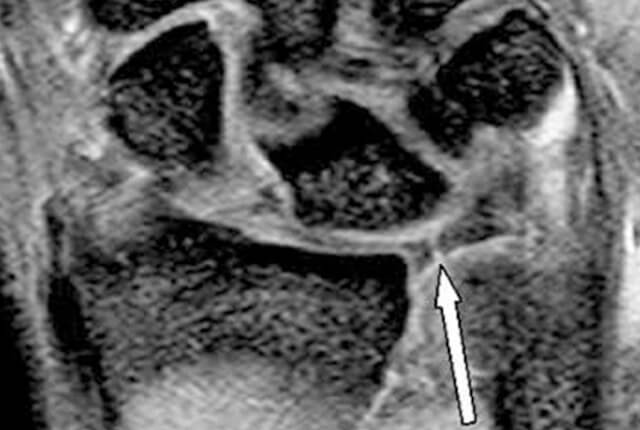

• MRIでTFCC損傷所見

MRIでTFCC損傷所見